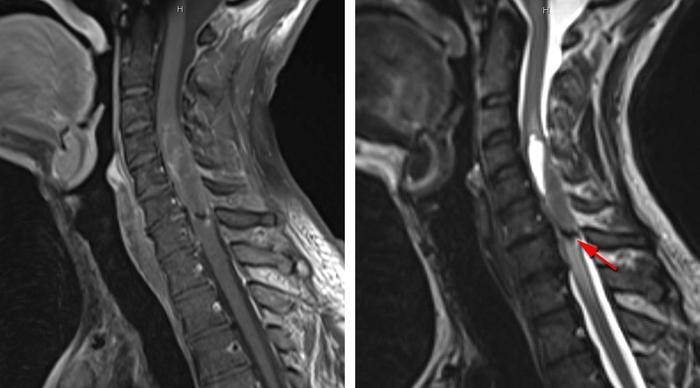

2:颈段室管膜瘤伴有少量强化,肿瘤下极可见一小出血灶(箭头所示,右图)。

4:图中所示为伴囊变的胸髓毛细胞型星形细胞瘤,此病理类型肿瘤主要位于脊髓背侧,呈偏心性生长。不同于更高级别的胶质瘤,毛细胞型星形细胞瘤多边界清楚,表现为压迫脊髓而非浸润性生长。